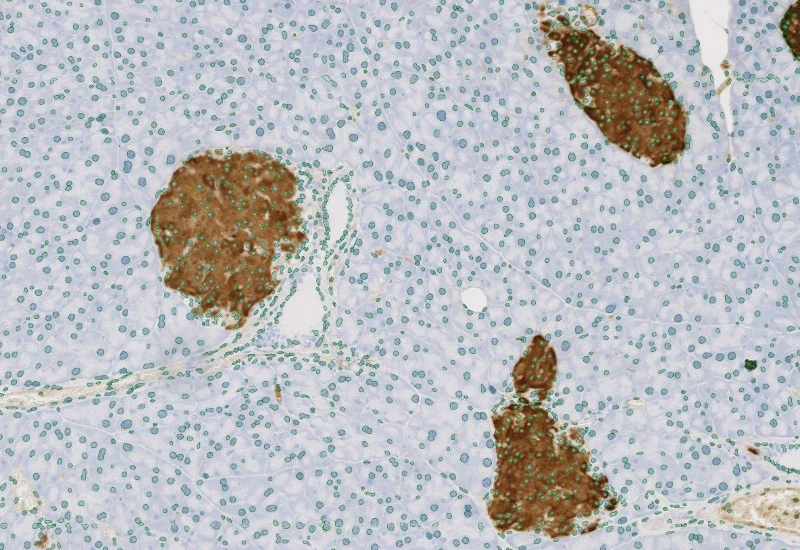

Detect IHC/HC-stained metastructures (e.g. islets, tumor, stroma) and segment single cells into nucleus, perinuclear area, and/or cytoplasm, classify cells inside/outside metastructures, and measure up to 20 intensity, statistic, and morphometric parameters per area and compartment.

insulin islets, pancreas, immunohistochemistry, beta-cells, brightfield

The IHC Meta Cells App combines the detection of IHC/HC stained metastructures (e.g. Langerhans islets, Tumor - Stroma) with single cell detection (segmentation of cells into nucleus, and/or perinuclear area and/or cytoplasm). Detected cells can be classified and visualized as being either within or outside of detected metastructures. Each detected area and cell compartment is measured for up to 20 intensity, statistic and morphometric parameters.